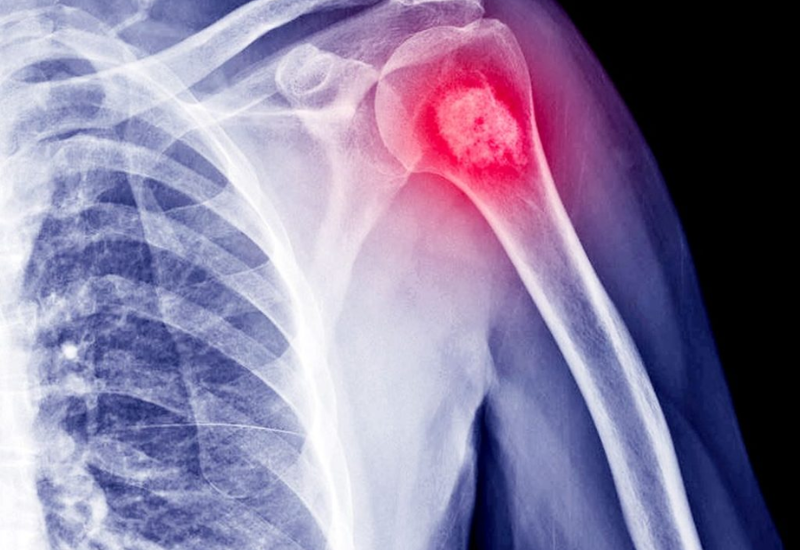

- X-quang: Đây là bước khảo sát đầu tiên giúp phát hiện sớm bất thường về cấu trúc xương. Hình ảnh X-quang cho phép bác sĩ nhận biết vị trí, kích thước khối u và mức độ tổn thương của vùng xương bị ảnh hưởng.